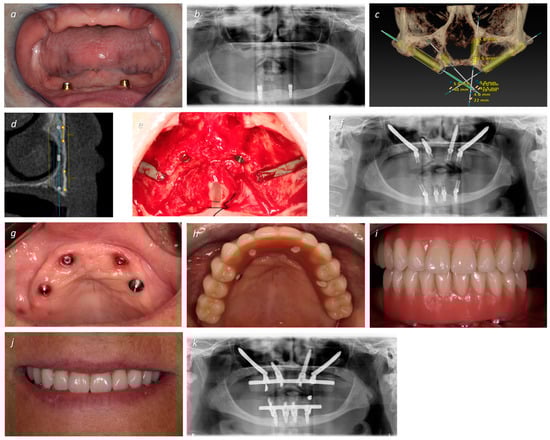

| 2 | EM 0° 5 × 40 | T 3.75 × 22.5 | T 3.75 × 22.5 | EM 0° 5 × 40 | 56 | F | 3 | I | NG | 50 |